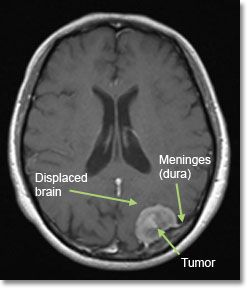

腦膜瘤的臨床表現(xiàn)有哪些?腦膜瘤是來(lái)源于包裹蛛網(wǎng)膜的腦膜上皮細(xì)胞的腫瘤。因此,發(fā)生在腦實(shí)質(zhì)外的腦膜瘤是軸外腫瘤。女性比男性更常見,65%的確診...